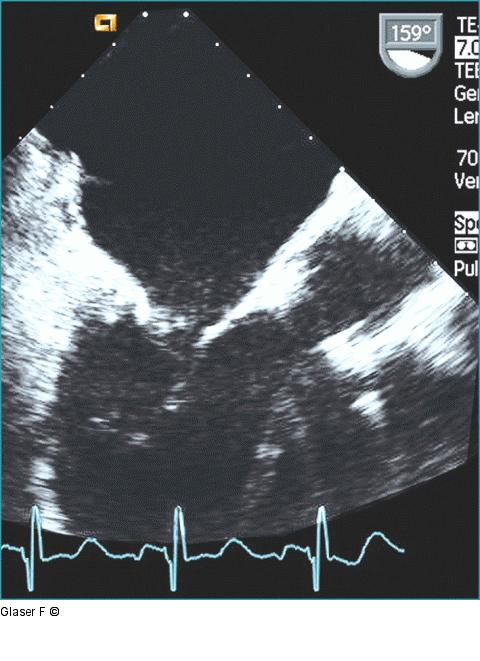

Abbildung 10: Aorta ascendens Ascendensdurchmesser nur 2,6 cm. |

Abbildung 10: Aorta ascendens

Ascendensdurchmesser nur 2,6 cm. |